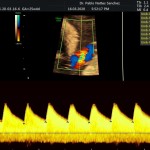

- La vitalidad y el bienestar fetal (Doppler).

- El Doppler de las arterias uterinas maternas y determinación de riesgo para pre eclampsia severa.